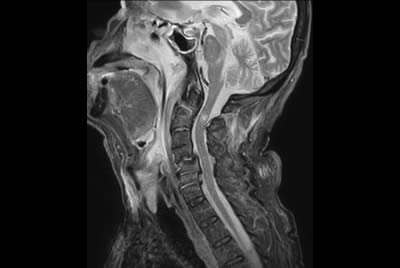

Cervical Spine - Cord lesion